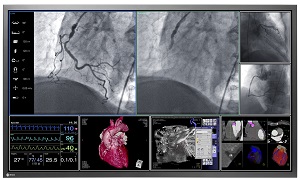

手術室では、X線透視画像、内視鏡画像、心拍数など様々な医療情報の参照が必要であり、一般的には複数のモニターを並べ、それぞれの画面に各情報を表示している。同社は、情報の管理と操作の負荷軽減のため、様々なシステムから送信される医療情報を収集し、管理する信号配信マネージャーと、これらの医療情報を一画面に表示する60インチの大型モニターを販売している。今回さらに58型モニターを追加し、手術室の規模に応じて選べるラインナップを拡充する。

今回発売する「RadiForce LS580W」は、対角58インチの大画面に高解像度8メガピクセル(3840×2160=829万画素)の情報表示が可能。同じ解像度表示が可能な旧機種56インチモニターLS560Wから画面を大型化しつつ、ベゼル(画面の外枠)を細くすることで、LS560Wと同等の外形寸法と質量を実現した。